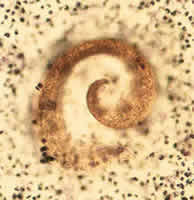

A 4-year-old girl from Mexico City was seen by her pediatrician for chronic

diarrhea of three months duration. Her mother is HIV-positive and

was undergoing therapy for HIV at the time of the examination. A

smear of the girl's stool was stained with Chromotrope 2R and examined

for ova and parasites. In the smear, oval-shaped objects were observed

(1000×, indicated by arrows in Figure A). The objects averaged

1.3 to 2.7 micrometers in diameter. What is your diagnosis? Based

on what criteria? Would you recommend any other laboratory tests?